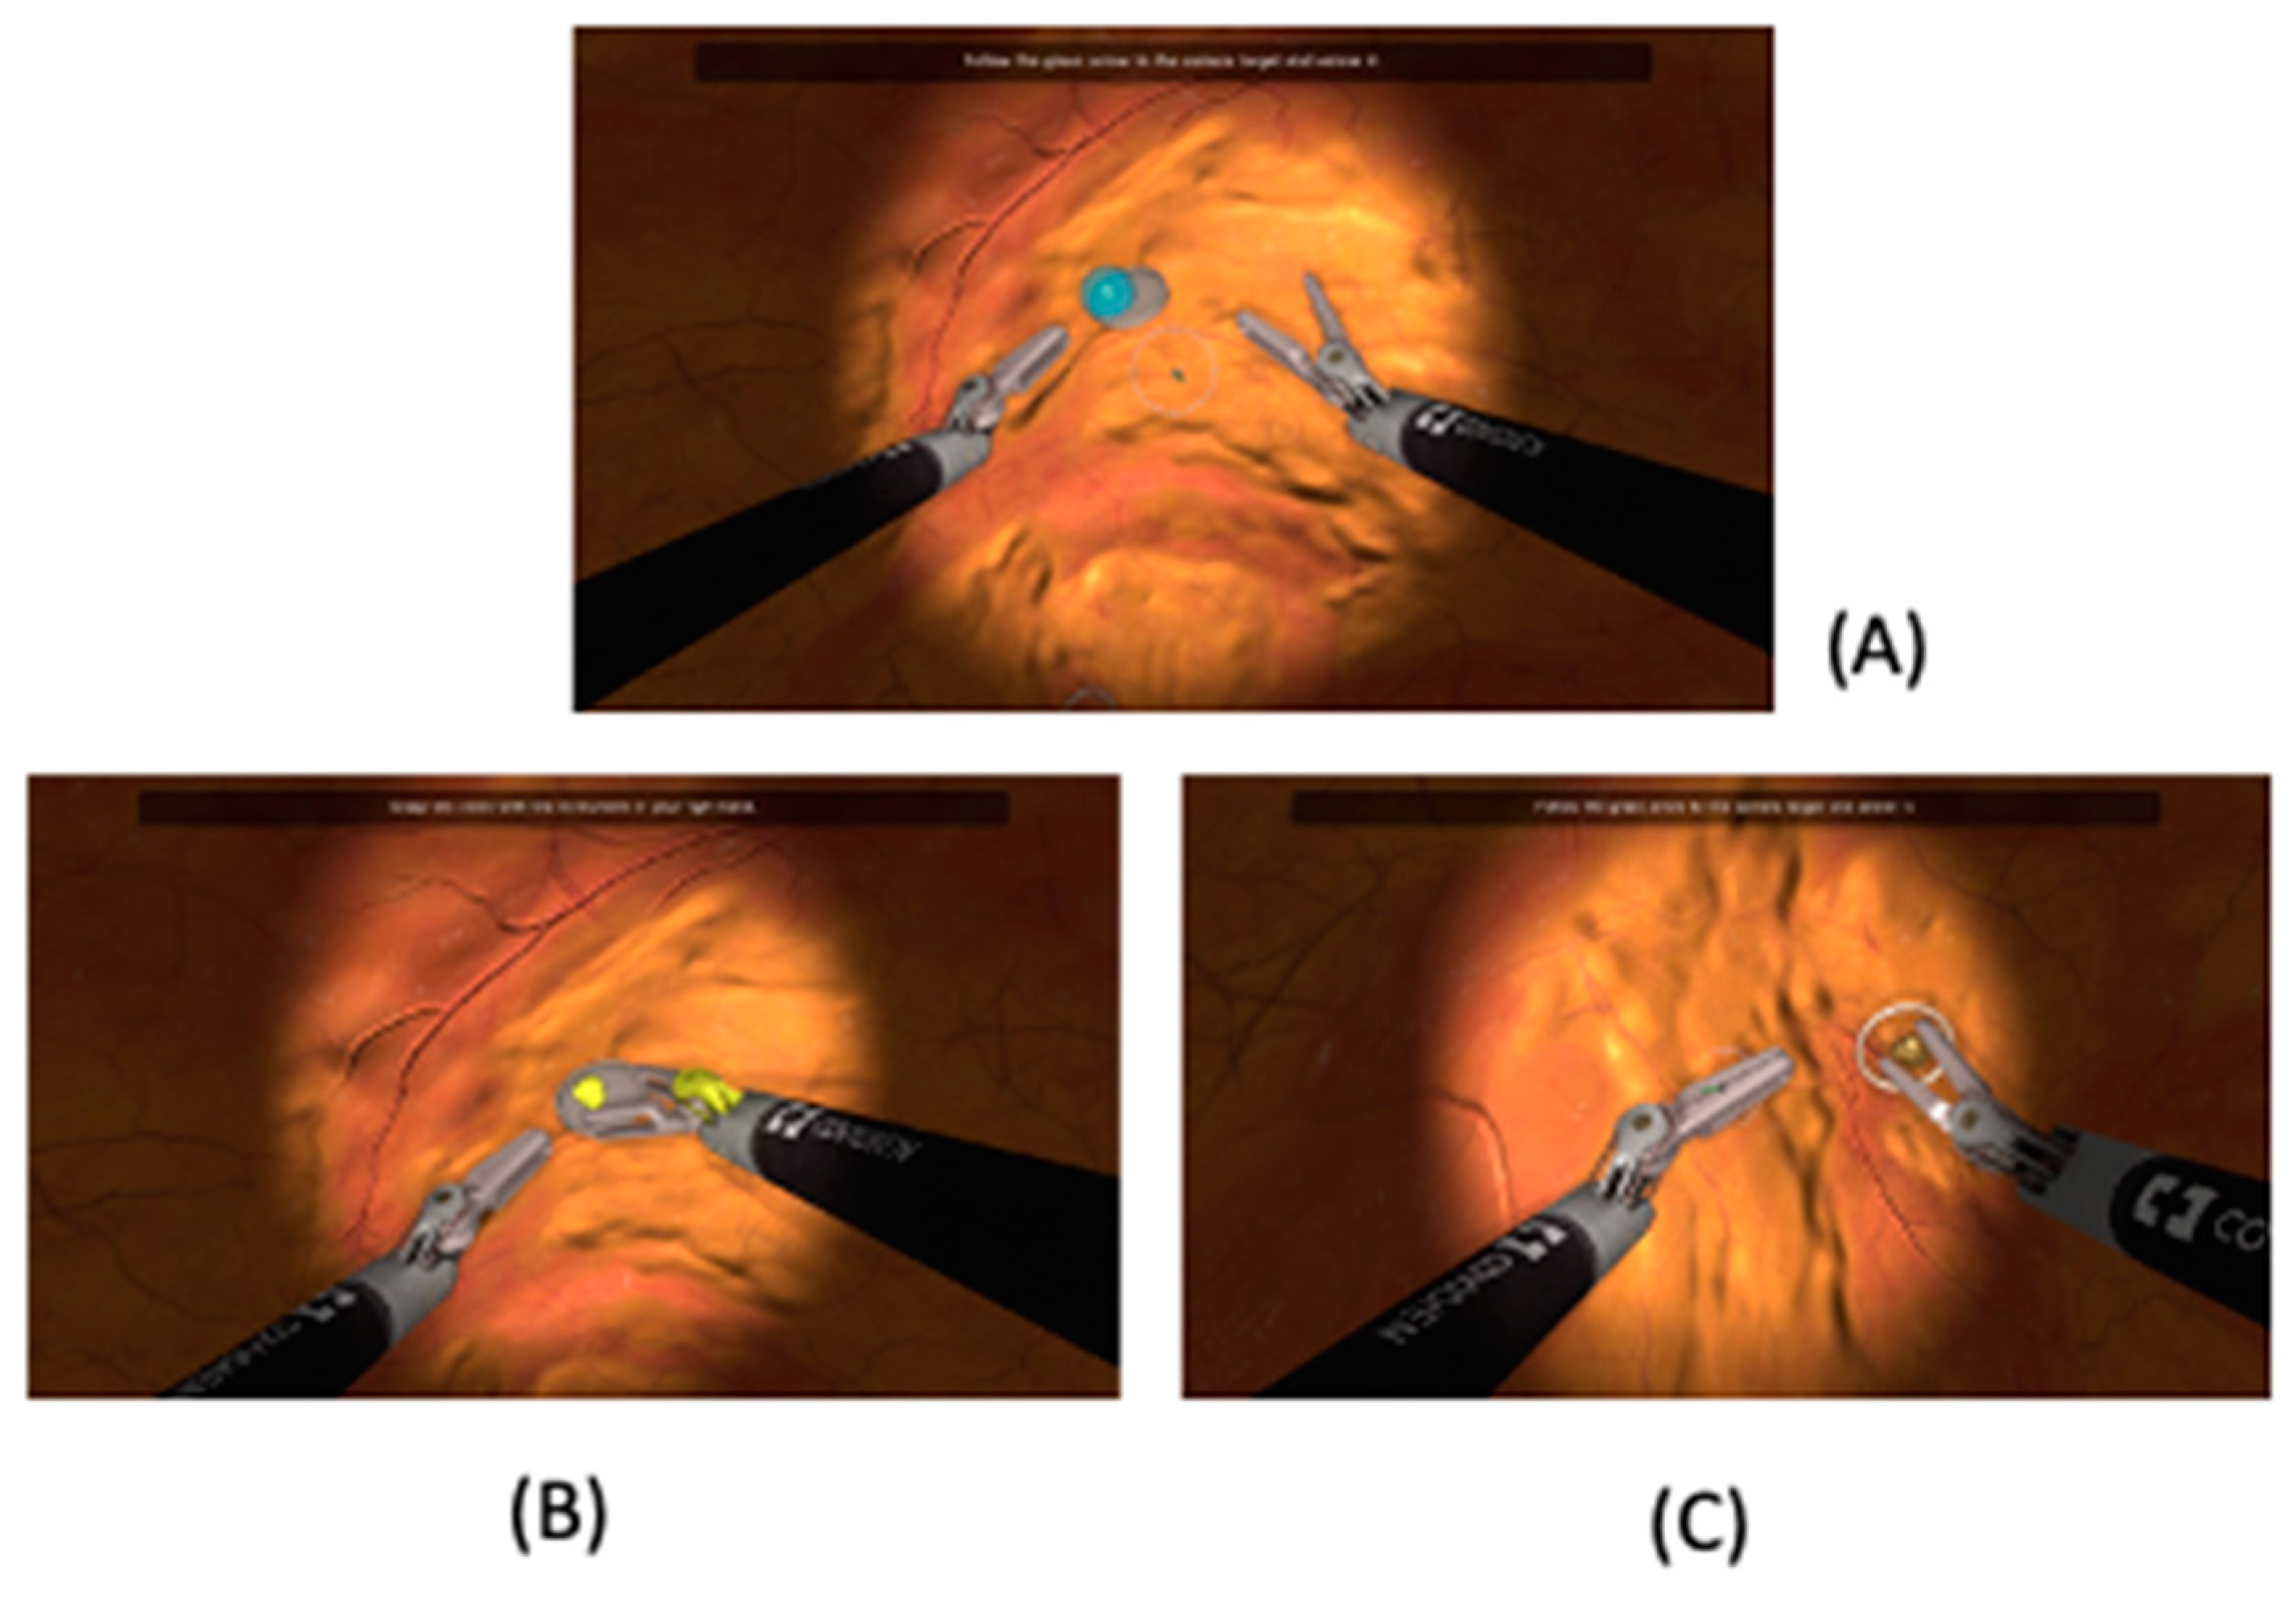

2.2. Training Session